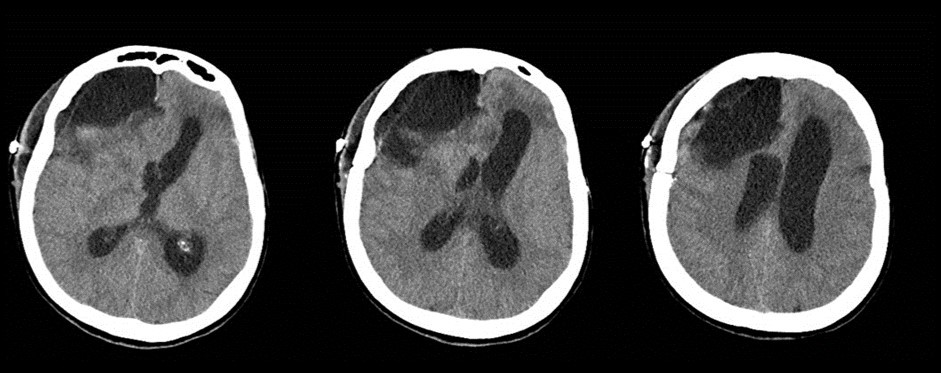

A 65 years-old woman with no relevant medical history was carried to the emergency department of another institution for the sudden onset of headache and vomiting, followed by loss of consciousness. She underwent a cerebral CT scan, that showed diffuse SAH in the basal cisterns and anterior interemispheric fissure (Figure 1). The CT angiogram displayed a single aneurysm of the anterior communicating artery, that local radiologists considered unfavorable for endovascular treatment. The patient was therefore surgically managed, with left pterional craniotomy for aneurysm clipping and right external ventricular drain (EVD) positioning. In the following days the woman reacquired alertness; the EVD was removed without need of permanent shunting and she was transferred to rehabilitation four weeks after the operation in quite good conditions.

Figure 1.Non-contrast axial CT scan showing thick subarachnoid hemorrhage in the basal cisterns and in the frontal interemispheric space

The clinical and radiological features of these two diseases are perfectly known to neurosurgeons; anyhow our case shows that trouble rises when they do occur simultaneously. The patient we described had initially acute signs due to SAH and later signs that were incorrectly interpreted as SAH-related. The tumor was almost invisible -because of its likely small volume and thick SAH- in the first CT performed (Figure 1). Analyzing the early follow-up CT (Figure 2) anyway things do not seem so clear. In the frontal region remained too much fogging close to the midline; the asymmetric distribution of such alteration should had point out a problem, but everybody kept thinking to a “simple” post-hemorrhagic condition, due to ventricular enlargement and focal ischemia. The initial mental impairment of that period was equally attributed to a normal SAH result with moderate hydrocephalus. The proper diagnosis of glioma happened late, and the patient was at that point unable to have significant benefits from surgery.